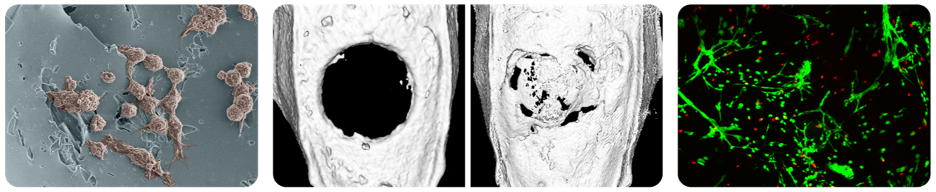

- Critically-sized bone defects are conventionally treated with patient-derived bone grafts; as such, "off-the-shelf" bone replacement therapies would improve patient quality of life and reduce healthcare costs.

- Though newer composites with inorganic ceramics and biodegradable synthetic polymers have shown promise as osteoinductive scaffolds, many conventional polyester-based systems are prone to autocatalytic degradation and premature implant failure in preclinical testing.

- To combat the disconnect between bone regeneration rates and scaffold degradation kinetics, our lab will seek to develop a cell-degradable bone substitute.

- A specifically cell-degradable implant will marry implant resorption with healing kinetics, thus preventing premature implant failure and improving bone regeneration outcomes.